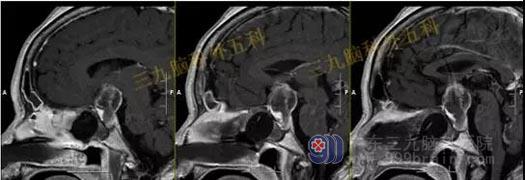

头部MR检查结果:鞍内及鞍上示一占位性病变,其内信号混杂,呈等或稍长T1稍长T2信号影,其内夹杂小片状短T1长T2信号影,增强后病灶呈明显不均匀强化;病灶范围约1.6cm×1.3cm×2.0cm;视交叉受压上抬,垂体柄受压右偏。

检查结果:鞍内及鞍上占位性病变,考虑为垂体大腺瘤合并卒中。

手术过程:患者今日在全麻下行内镜经鼻蝶鞍区垂体腺瘤切除术,术中肿瘤全切,垂体保护良好。

头部MR检查提示:鞍区病变已切除。